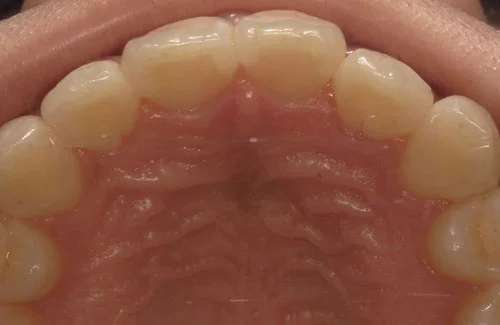

<症例7>歯がガタガタで噛み合わせが悪くお悩み

抜歯無し・マウスピースのみで矯正した症例です。

もともと歯列弓が非常に狭く、V字に近い形をしていたので噛み合わせも非常に不安定でした。

また、下顎前歯部がかなり上の方に生えていたため、下の前歯が上の前歯を突き上げてしまい出っ歯の状態になっていました。

現在では見た目はもちろん、臼歯の噛み合わせも改善しております。

奥歯の患者様も大喜びでした。

患者様と症状

主訴:歯のガタガタ、噛み合わせが悪い

性別・年齢:20代女性

問題点:叢生(重度)、V字歯列弓、ディープバイト

診断:前歯部の叢生を伴うアングルⅠ級、骨格性Ⅰ級の不正咬合

主なリスク:臼歯の移動に伴い一時的に咬合しにくくなる、歯肉退縮

症状:叢生(そうせい) 過蓋咬合(かがいこうごう)

治療内容

治療期間:1年10ヶ月

治療費用:990,000円(税込)

プラン:Full2プラン

抜歯:無し

再診治療費:無し

追加治療費:無し

保定装置費:無し

治療前後の写真